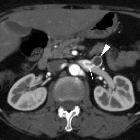

Asymptomatic

left renal vein aneurysm with thrombosis. Multiplanar reformatted images (b..d) from portal venous phase acquisition depicted the lesion (arrowheads) as a saccular outpouching of the left renal vein (*), with internal nonenhancing tissue representing intraluminal thrombus.